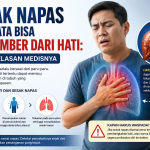

Sesak Napas Ternyata Bisa Bersumber dari Hati: Ini Penjelasan Medisnya

Pola makan sehat memainkan peran penting dalam menjaga kesehatan mental. Makanan yang kita konsumsi tidak hanya memengaruhi fisik, tetapi juga kesejahteraan mental kita. Namun, kesehatan tubuh tidak berhenti pada otak dan suasana hati saja. Organ hati juga memiliki peran besar dalam menjaga keseimbangan tubuh, termasuk sistem pernapasan infokesehatanhati.id. Tidak banyak yang menyadari bahwa gangguan pada […]